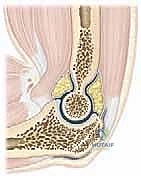

التشريح الوظيفي: لماذا يميل مفصل المرفق إلى التيبس؟

لفهم مشكلة تيبس المرفق، يجب أن نفهم أولاً طبيعة هذا المفصل المعقد. مفصل المرفق ليس مفصلاً بسيطاً، بل هو مفصل مركب يتكون من ثلاثة تمفصلات أساسية داخل محفظة مفصلية واحدة:

1. المفصل العضدي الزندي (Humeroulnar Joint): المسؤول الأساسي عن حركتي الثني (Flexion) والمد (Extension).

2. المفصل العضدي الكعبري (Humeroradial Joint): يساهم في الثني والمد وكذلك في دوران الساعد.

3. المفصل الكعبري الزندي القريب (Proximal Radioulnar Joint): المسؤول عن حركتي الكب (Pronation) والاستلقاء (Supination) للساعد واليد.

السر وراء التيبس:

مفصل المرفق يتميز بتطابق عظمي شديد الإحكام ومحفظة مفصلية (Joint Capsule) حساسة للغاية. أي صدمة، نزيف داخلي، أو التهاب يؤدي بسرعة إلى استجابة تليفية (Fibrotic Response). المحفظة المفصلية تنكمش وتتسمك، وتتكون التصاقات وندبات داخلية تسلب المفصل مرونته. بالإضافة إلى ذلك، فإن قرب الأربطة والعضلات من مركز المفصل يجعل أي تقلص فيها يؤثر مباشرة على المدى الحركي.